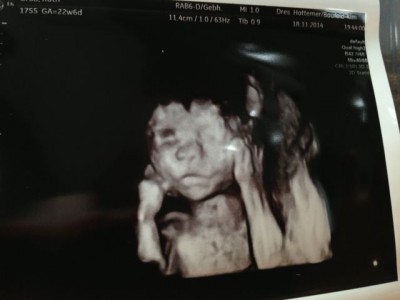

Die VU bei meiner FÄ war wieder toll. Die Krabbe hat beim US aber auch wieder alles gegeben und wieder einen ihrer Füße in der Mangel gehabt